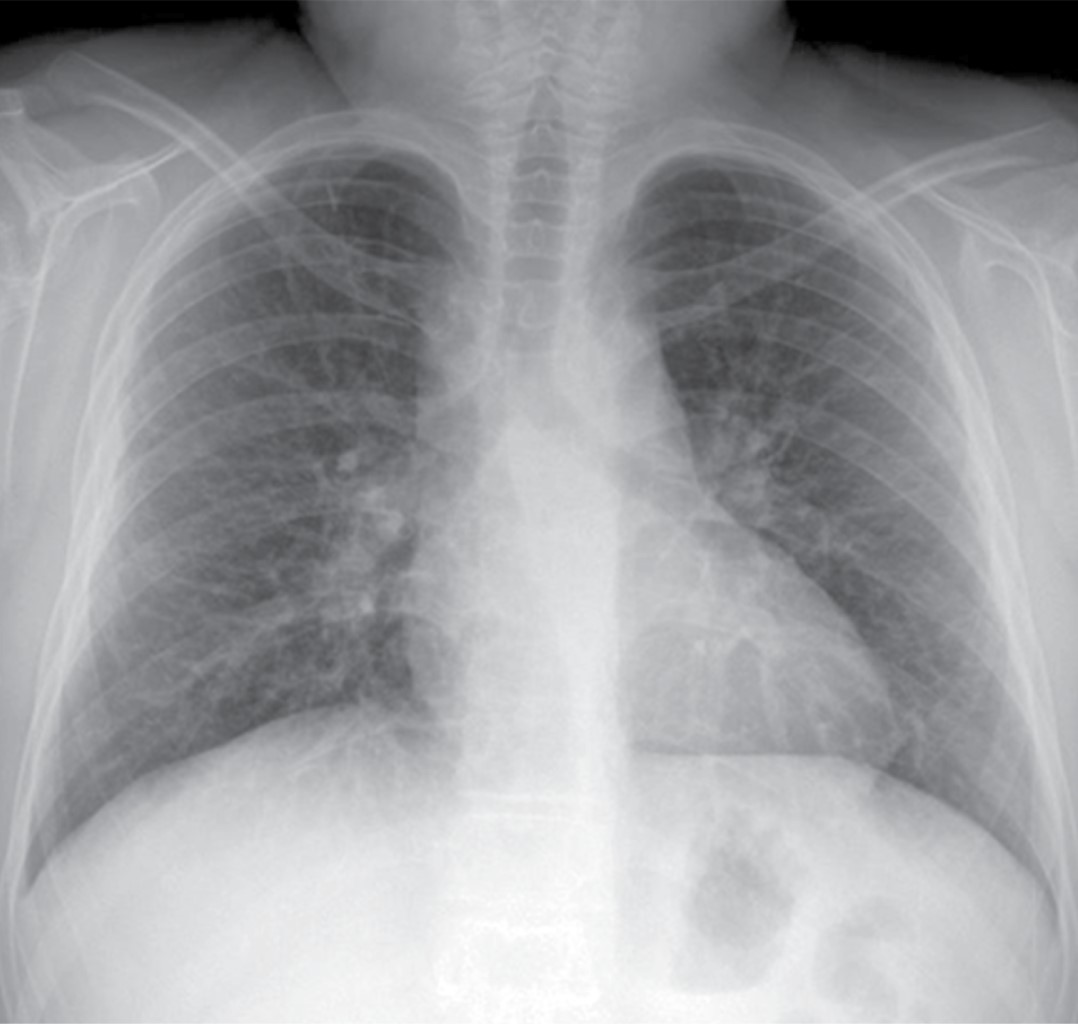

La radiografía de tórax mostró ensanchamiento mediastinal y un patrón intersticial grueso a expensas de intersticio perilobulillar bilateral y difuso, casi simétrico con algunas imágenes nodulares también difusas (Figura 9). En la TACAR contrastada se corrobora el patrón intersticial perilobulillar con nódulos difusos con discreto predominio subpleural así como zonas de atelectasia bilateral subpleurales y en lóbulo medio (Figura 10). En la ventana mediastinal se demuestran crecimientos ganglionares paratraqueales de predominio derecho, en ventana aortopulmonar y axilar bilateral. A nivel abdominal lesiones nodulares hipodensas múltiples hepatoesplénicas sugestivas de granulomas (Figura 11). Se realizó biopsia de piel en cara, la cual mostró dermatitis granulomatosa epitelioide no caseificante, compatible con sarcoidosis (Figura 12).

Las pruebas de función respiratoria iniciales mostraron un patrón sugestivo de restricción moderada, sin respuesta significativa al broncodilatador. La broncoscopia mostró traqueobronquitis leve y gastritis antral, baciloscopias en serie de tres y prueba de PPD reportadas negativas. La biopsia de piel reveló granulomas desnudos compatibles con sarcoidosis. Para la uveítis recibió prednisona ocular al 1%. Fue tratado por otro servicio con tres pulsos de metilprednisolona a 30 mg/kg/día, prednisona oral a 0.7 mg/kg/día y micofenolato de mofetilo 42 mg/kg/día (1 g VO cada 12 horas) sin respuesta. Cambiamos a prednisona en dosis de 1 mg/kg/día y metotrexato a 15 mg/m2/semana, hubo respuesta favorable desde las cuatro primeras semanas de tratamiento; la enfermedad está inactiva, pero el paciente cursa con tos, disnea, cianosis distal, y baja saturación de O2, todo lo anterior traduce un daño pulmonar permanente (Figuras 13 y 14).

La radiografía de tórax es anormal en 90% de los casos. Los dos hallazgos más característicos son la linfadenopatía mediastinal bilateral acompañada de enfermedad intersticial nodular del pulmón, éstos sirven para la estadificación de la enfermedad,5,8 siendo la TACAR la herramienta más valiosa para el diagnóstico (Tabla 1).

Las adenopatías paratraqueales bilaterales e hiliares son las más comunes. Los patrones radiológicos parenquimatosos más comunes son las opacidades reticulonodulares (90%) en las zonas superiores del pulmón, afección alveolar y fibrosis pulmonar. El patrón miliar es raro a cualquier edad.1,5,8

Nuestros casos se clasifican en el estadio II, ya que en la TACAR se detectó adenopatía hiliar bilateral con infiltrados pulmonares (Tabla 1).